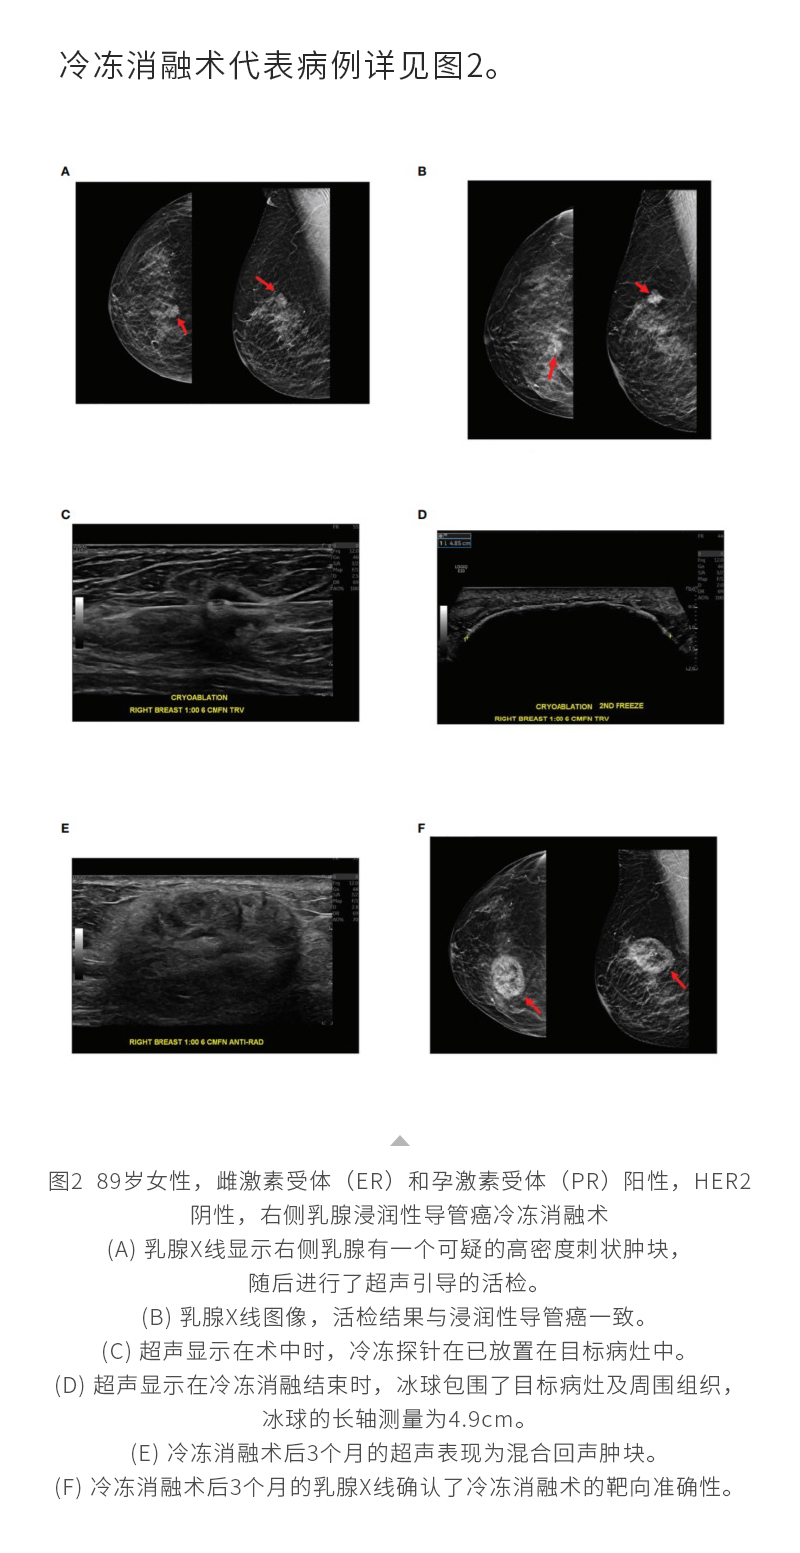

冷凍消融乳腺癌——【海杰亞科研資訊】第287期